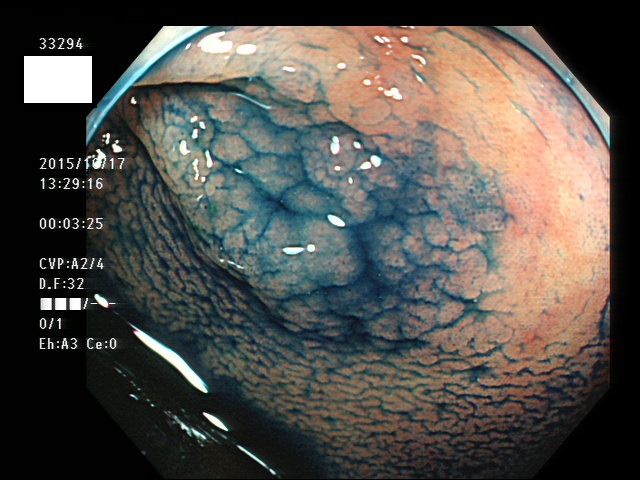

上記100名より抽出した平坦・陥凹型腺腫(=癌化の危険が高いが見落としやすい病変)の内視鏡写真